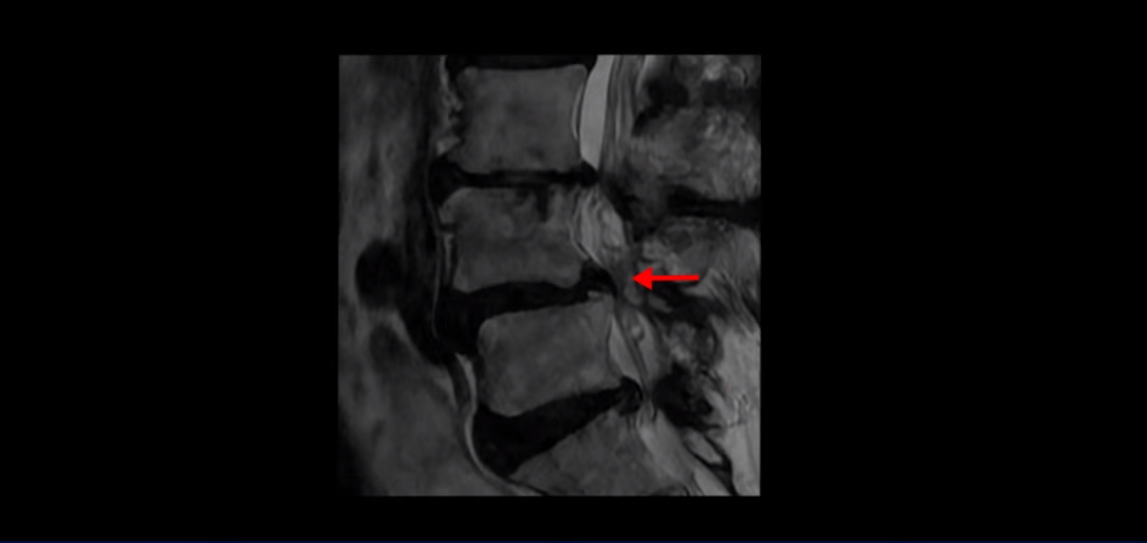

제가 먼저 이분 MRI를 보고 설명해 드린 후 어떻게 이런 분들을 수술 없이 허리 기능재활치료로 호전시킬 수 있는지 자세히 설명드리겠습니다. 이분 허리가 보시다시피 여러 마디가 퇴행되어 있고

4번 5번에는 뼈가 밀려 나간 전방전위증도 있습니다.

4번 5번 마디를 자세히 보면 심한 중심성 협착이 있어서 신경 구멍이 매우 좁아져 있습니다.